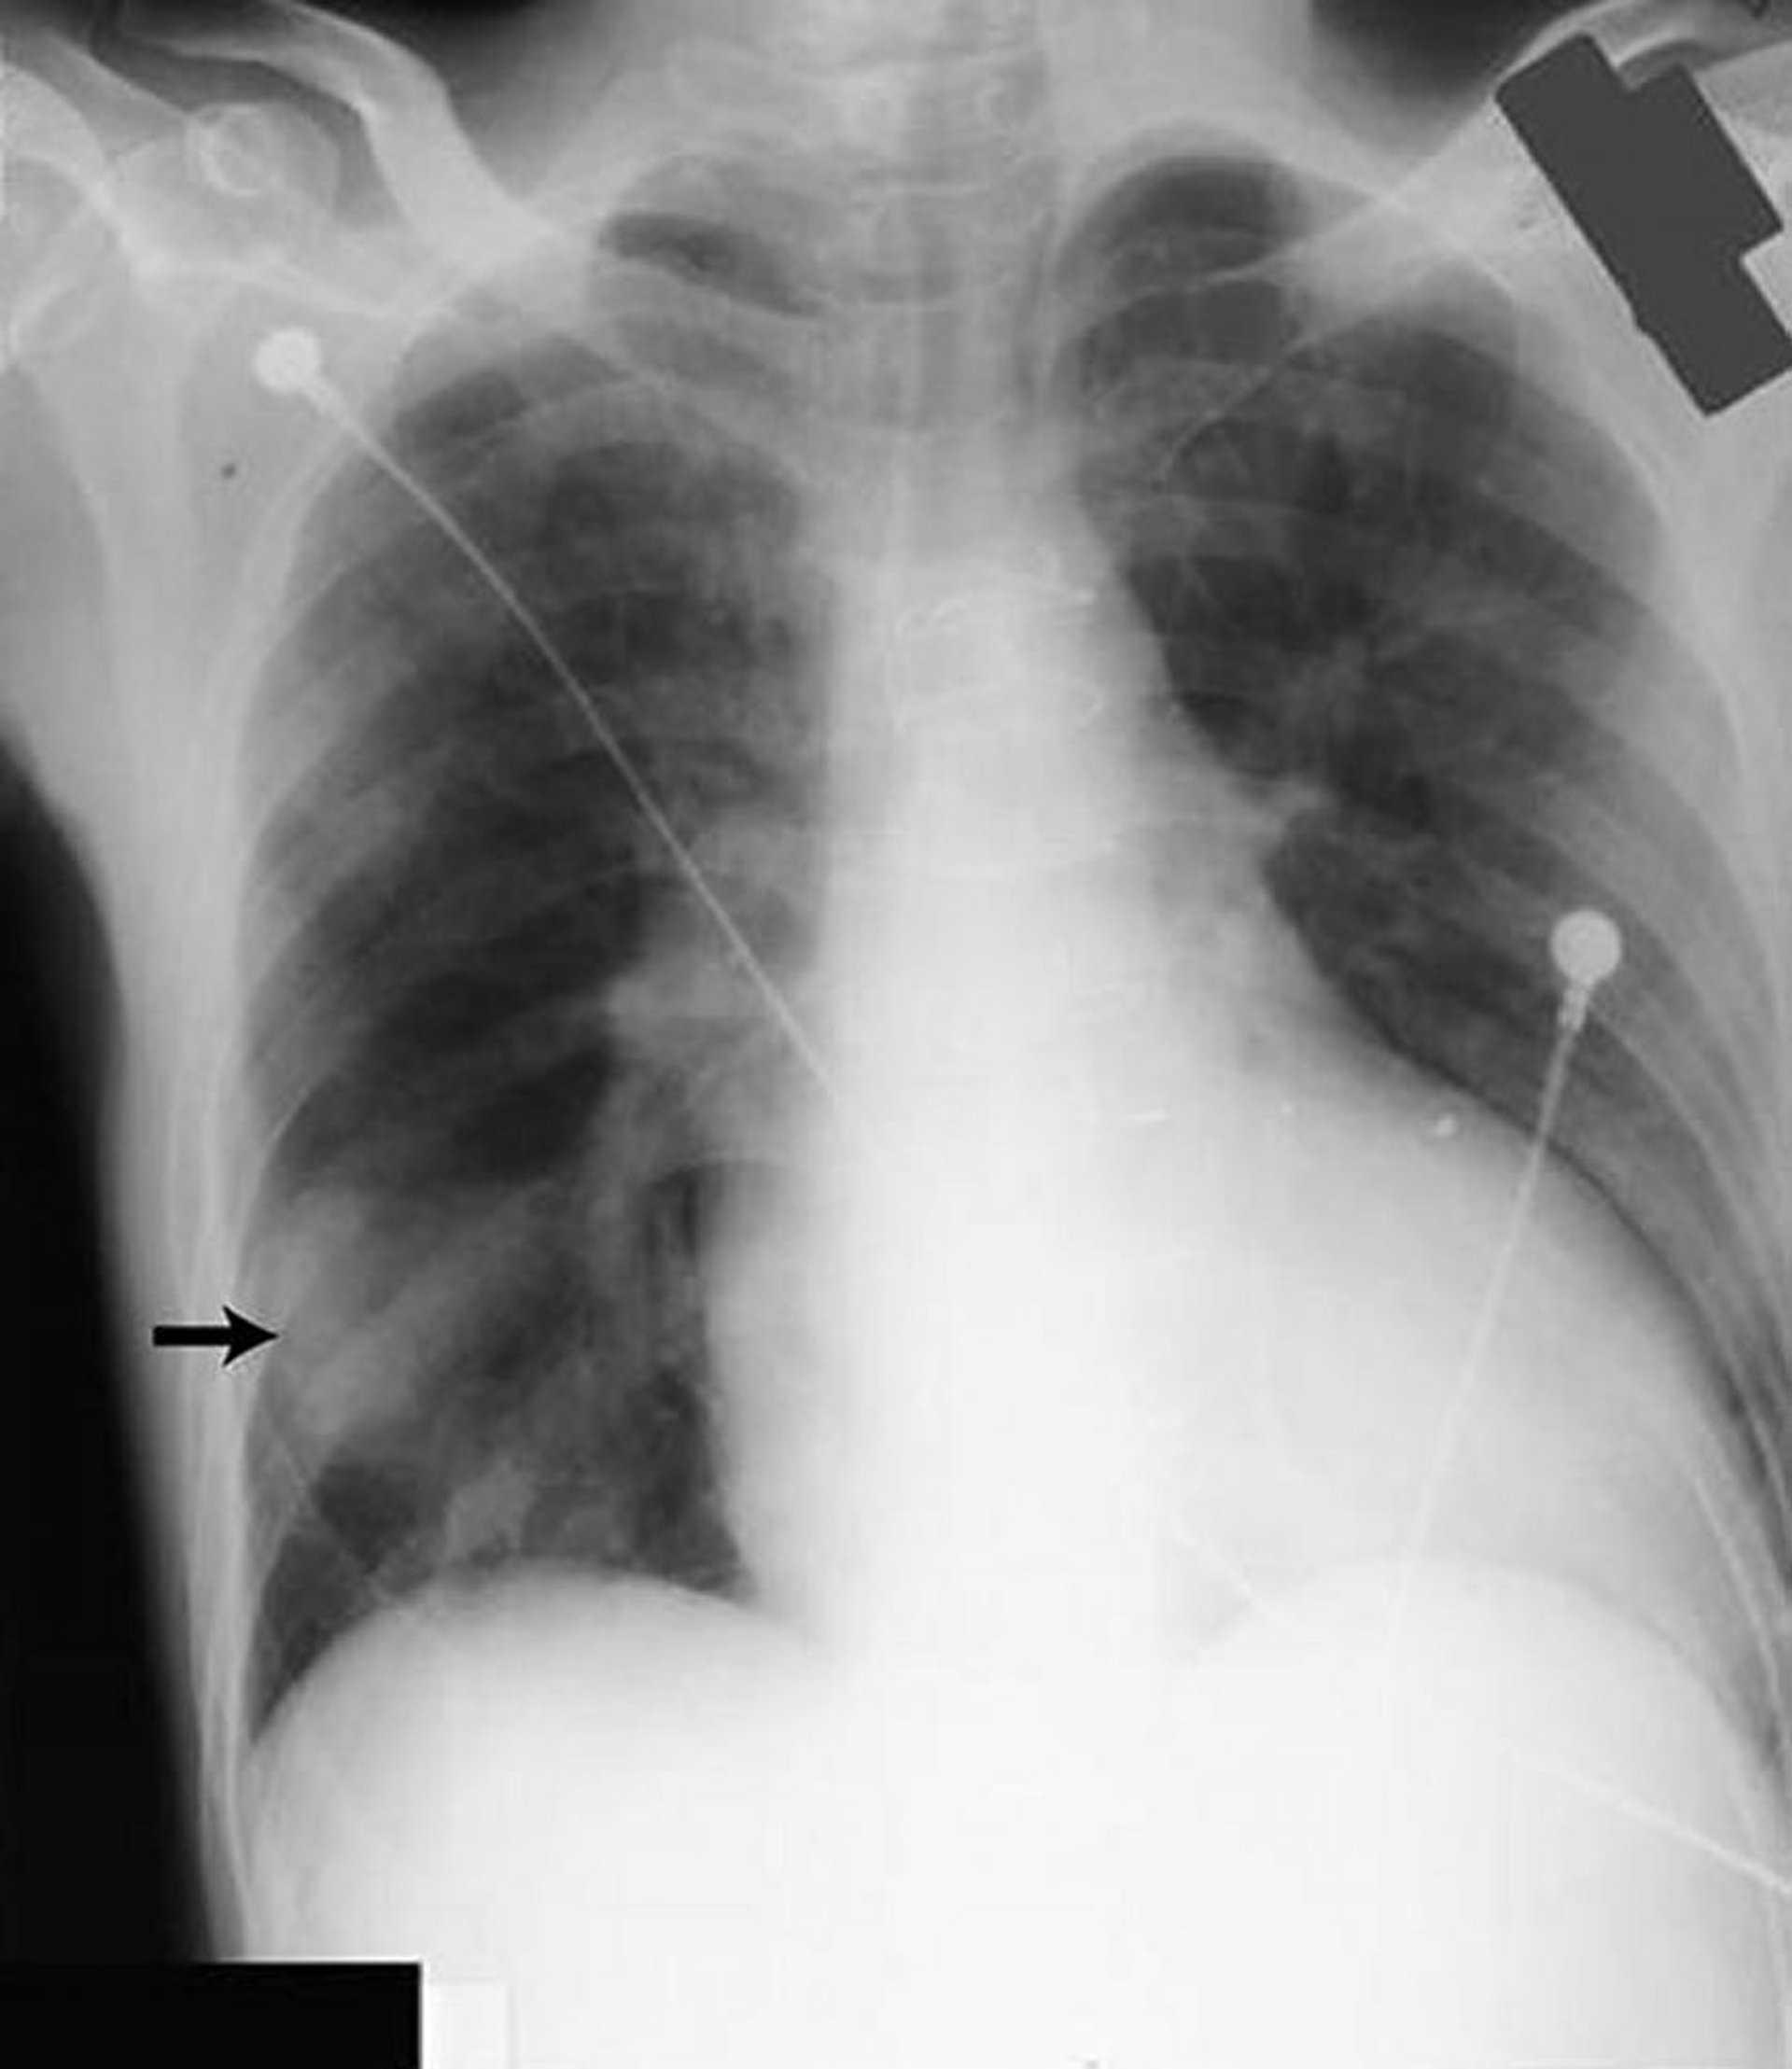

Наявність випоту

Chest radiograph is the first test performed to confirm the presence of pleural fluid. The lateral upright chest radiograph should be examined when a pleural effusion is suspected. In an upright radiograph, 75 mL of fluid blunts the posterior costophrenic angle. Blunting of the lateral costophrenic angle usually requires about 175 mL but may take as much as 500 mL. Lateral decubitus radiographs (with the side of the effusion down) may be able to detect small fluid volumes more easily than standard upright radiographs, particularly with a free-flowing effusion. Larger pleural effusions opacify portions of the hemithorax and may cause mediastinal shift; effusions > 4 L may cause complete opacification of the hemithorax and mediastinal shift to the contralateral side.

Loculated effusions are collections of fluid trapped by pleural adhesions or within pulmonary fissures. Further imaging (lateral decubitus radiographs, chest CT, or ultrasound) should be performed if it is unclear whether a radiographic density represents fluid or parenchymal infiltrates or whether suspected fluid is loculated or free-flowing; these tests are more sensitive than upright radiographs and can detect small fluid volumes. Loculated effusions, particularly those in the horizontal or oblique fissure, can be confused with a solid pulmonary mass (pseudotumor). They may change shape and size with changes in the patient’s position and the amount of pleural fluid.